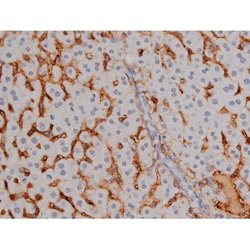

Invitrogen™ Phospho-NPM1 (Thr199) Polyclonal Antibody

Antibody detects endogenous levels of Nucleophosmin only when phosphorylated at Threonine 199.

| Applications | Immunohistochemistry (Paraffin), Western Blot, Immunocytochemistry |